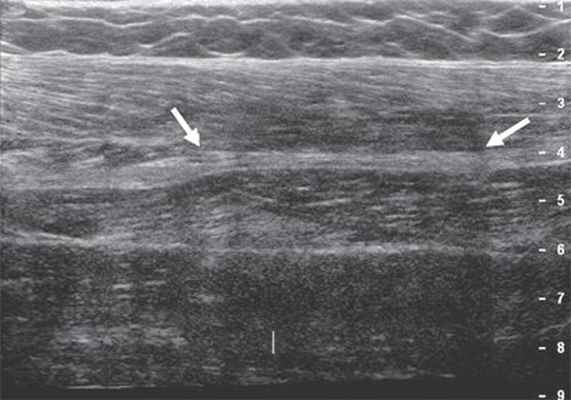

Рис. 4. Седалищный нерв (продольная проекция, панорамное сканирование) в средней трети бедра (стрелки).

В дистальных отделах бедра, чаще в верхнем углу подколенной ямки, нерв делится на две ветви: более толстую медиальную - большеберцовый нерв и более тонкую латеральную - общий малоберцовый нерв. Именно с этой области лучше всего начинать ультразвуковое исследование седалищного нерва и его ветвей.